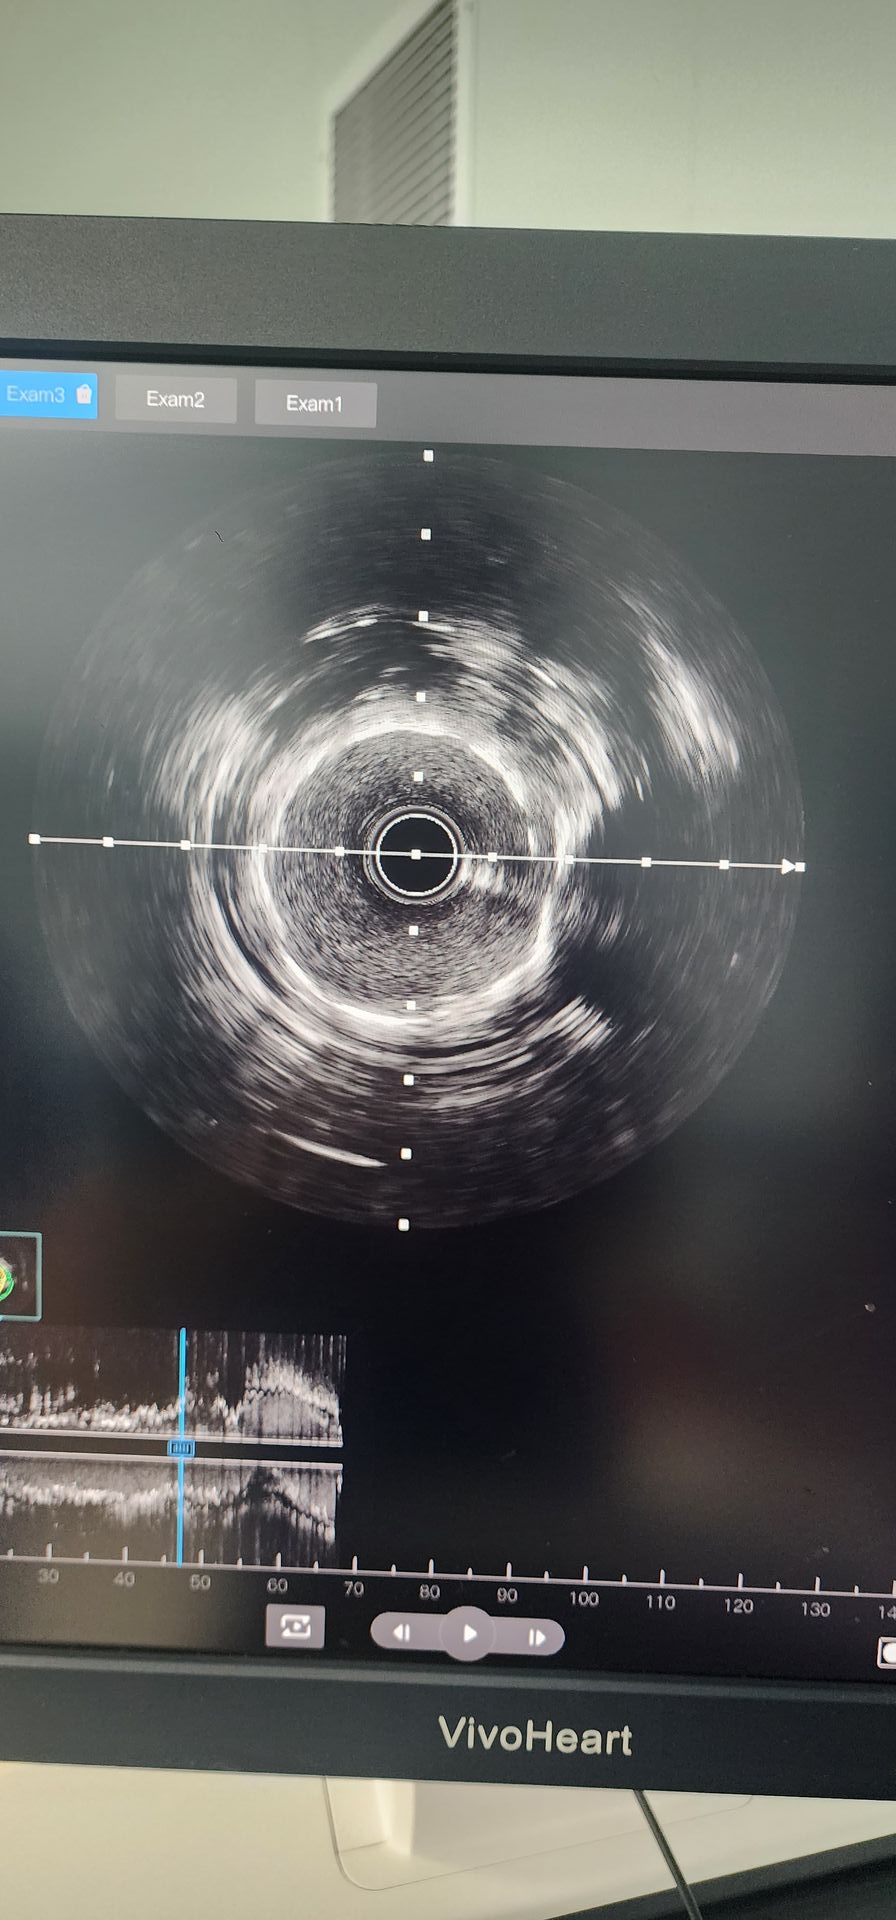

L'angiografia coronarica ha rivelato una grave calcificazione con stenosi del 95% nell'arteria circonflessa prossimale e stenosi calcificata dell'85 %-90% nell'arteria coronaria medio-destra.

Arteria circumflex prossimale: la pre-dilatazione iniziale con un palloncino 2.0 × 20 ha mostrato risultati scarsi. È stato quindi utilizzato un catetere di dilatazione del palloncino IVL coronarico 2,5 × 12 Lepu Vesscrack, che ha erogato quattro cicli, fratturando con successo la lesione calcificata. Dopo un significativo miglioramento della stenosi, è stato impiantato con successo uno stent 2,5 × 14, con risultati angiografici soddisfacenti.

Arteria coronarica medio-destra: la pre-dilatazione iniziale con un palloncino 2,5 × 20 ha comportato un miglioramento limitato. Un catetere di dilatazione del palloncino IVL coronarico 2,5 × 12 Lepu Vesscrack è stato quindi utilizzato per due cicli, migliorando significativamente la stenosi nella lesione calcificata. Uno stent 3.0 × 19 è stato quindi impiantato con successo, producendo risultati angiografici soddisfacenti.